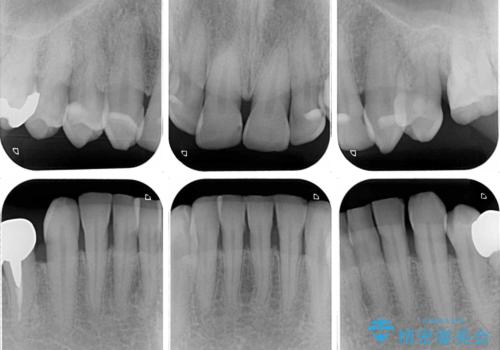

- 薬剤の影響で黄ばんでしまった前歯を気にして来院された患者様です。

奥歯の銀歯も気にはなるものの、口を開けたときに目立たないとのことで、上下ともに前歯を中心にオールセラミッククラウンにて補綴治療を行うこととしました。

咬合力が非常に強いため、就寝時には上下ともにマウスピースを使用していただくよう指導をしています。